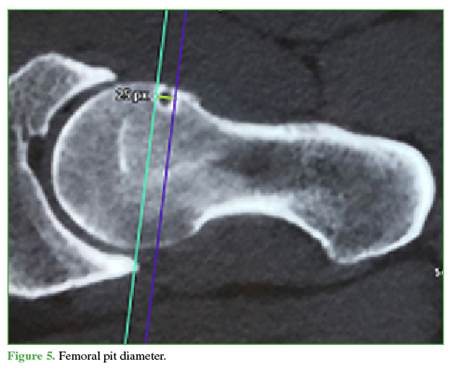

SP morphology: The following parameters were analyzed on axial oblique CT or arthro-MRI slices: 1) measured by a tangent from the anterior femoral cortex to the deepest point of the SP (Figure 4); 2) measured by a tangent from the proximal femoral border to the most distal point of the SP (Figure 5); 3) Shape: round, oval, or multilobulated; and 4) Rim: complete (cyst) or incomplete (notched).